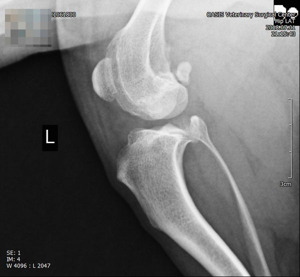

진단 방법

- 임상 증상과 이학적 검사(무릎의 불안정성 확인)

- 방사선(X-ray) 촬영

- 관절 초음파 검사 등 영상 진단

십자인대 파열 시 무릎의 변화

- 관절 불안정

십자인대가 끊어지면 경골이 앞으로 밀리면서 무릎 관절이 불안정해집니다. - 이로 인해 강아지는 뒷다리를 절거나 들고 다니게 되고, 정상적인 보행이 어려워집니다.

구조적 변화

- 정강이뼈의 전방 이동

십자인대가 끊어지면 정강이뼈가 앞쪽으로 밀려나 무릎 관절의 구조적 정렬이 무너집니다. - 무릎의 비정상적 움직임